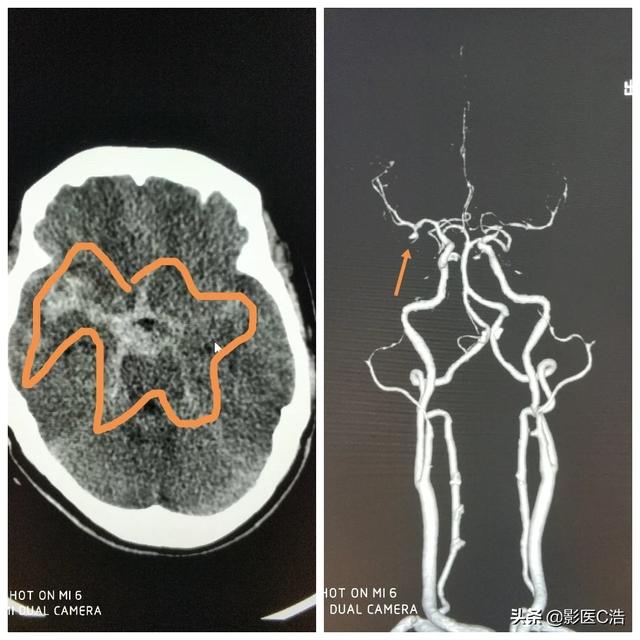

くも膜下出血の主な原因は頭蓋内動脈瘤と脳(脊髄)血管奇形であり、自然くも膜下出血の約70%を占め、次いで高血圧性動脈硬化症、喫煙性疾患、血液疾患などが挙げられる。自然くも膜下出血の全体的な予後は不良で、生存者の障害率は比較的高い。患者の多くは前兆症状を伴わない急激な発症で、激しい頭痛、羞明、吐き気、嘔吐、顔面蒼白、冷や汗などの症状が現れ、てんかん、めまい、頸肩痛、下肢痛を伴うものもあり、約半数の患者に興奮、錯乱、見当識障害などの精神症状が現れます。重症になると昏睡状態に陥り、脳ヘルニアを起こして死に至ることもある。以前、このような患者に出会ったことがある。25歳の少年で、フィットネストレーナーだったが、突然脳動脈瘤が破裂して出血し、長い間救命し、ようやく助かったが、予後は非常に悪い。下の写真は、脳動脈瘤が破裂し(右矢印)、出血(左の白い丸で囲んだ部分)している患者で、高血圧の既往歴があり、誰かと口論になり、突然地面に倒れた。